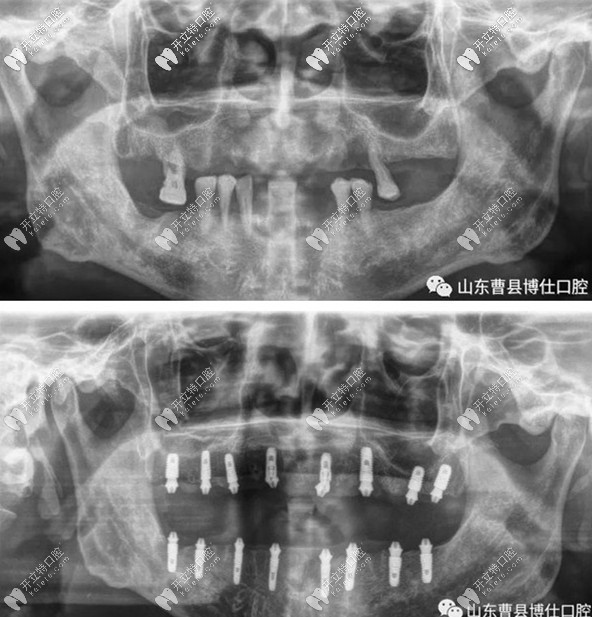

從資料上來看,他家是曹縣比較早完成全口即刻種植的口腔,說明牙科的種植實(shí)力還是很強(qiáng)的!